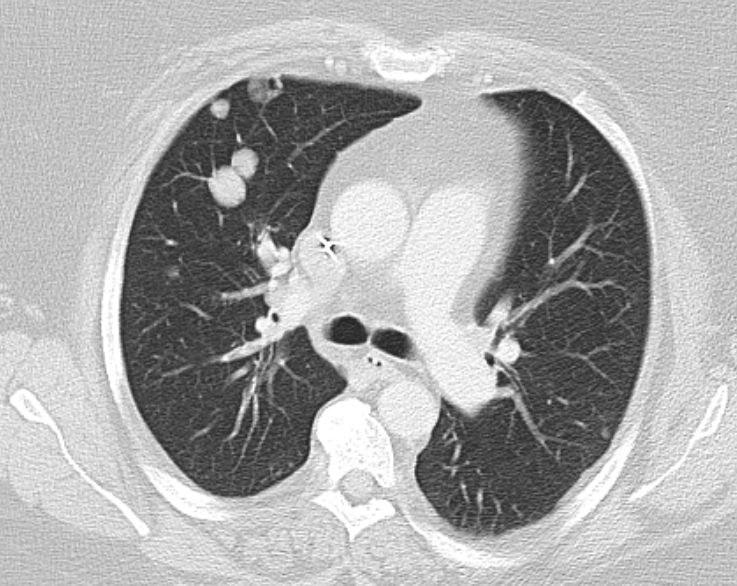

| Mediastinum | 71-jährige Frau, 3 Jahre nach radikaler

Hysterektomie wegen endometrioidem Corpuskarzinom pT1a pNo(0/48) Mo Lo Vo. Jetzt

Ösophagusstenose durch mediastinale Metastase. Zusätzlich Lungenmetastasen.